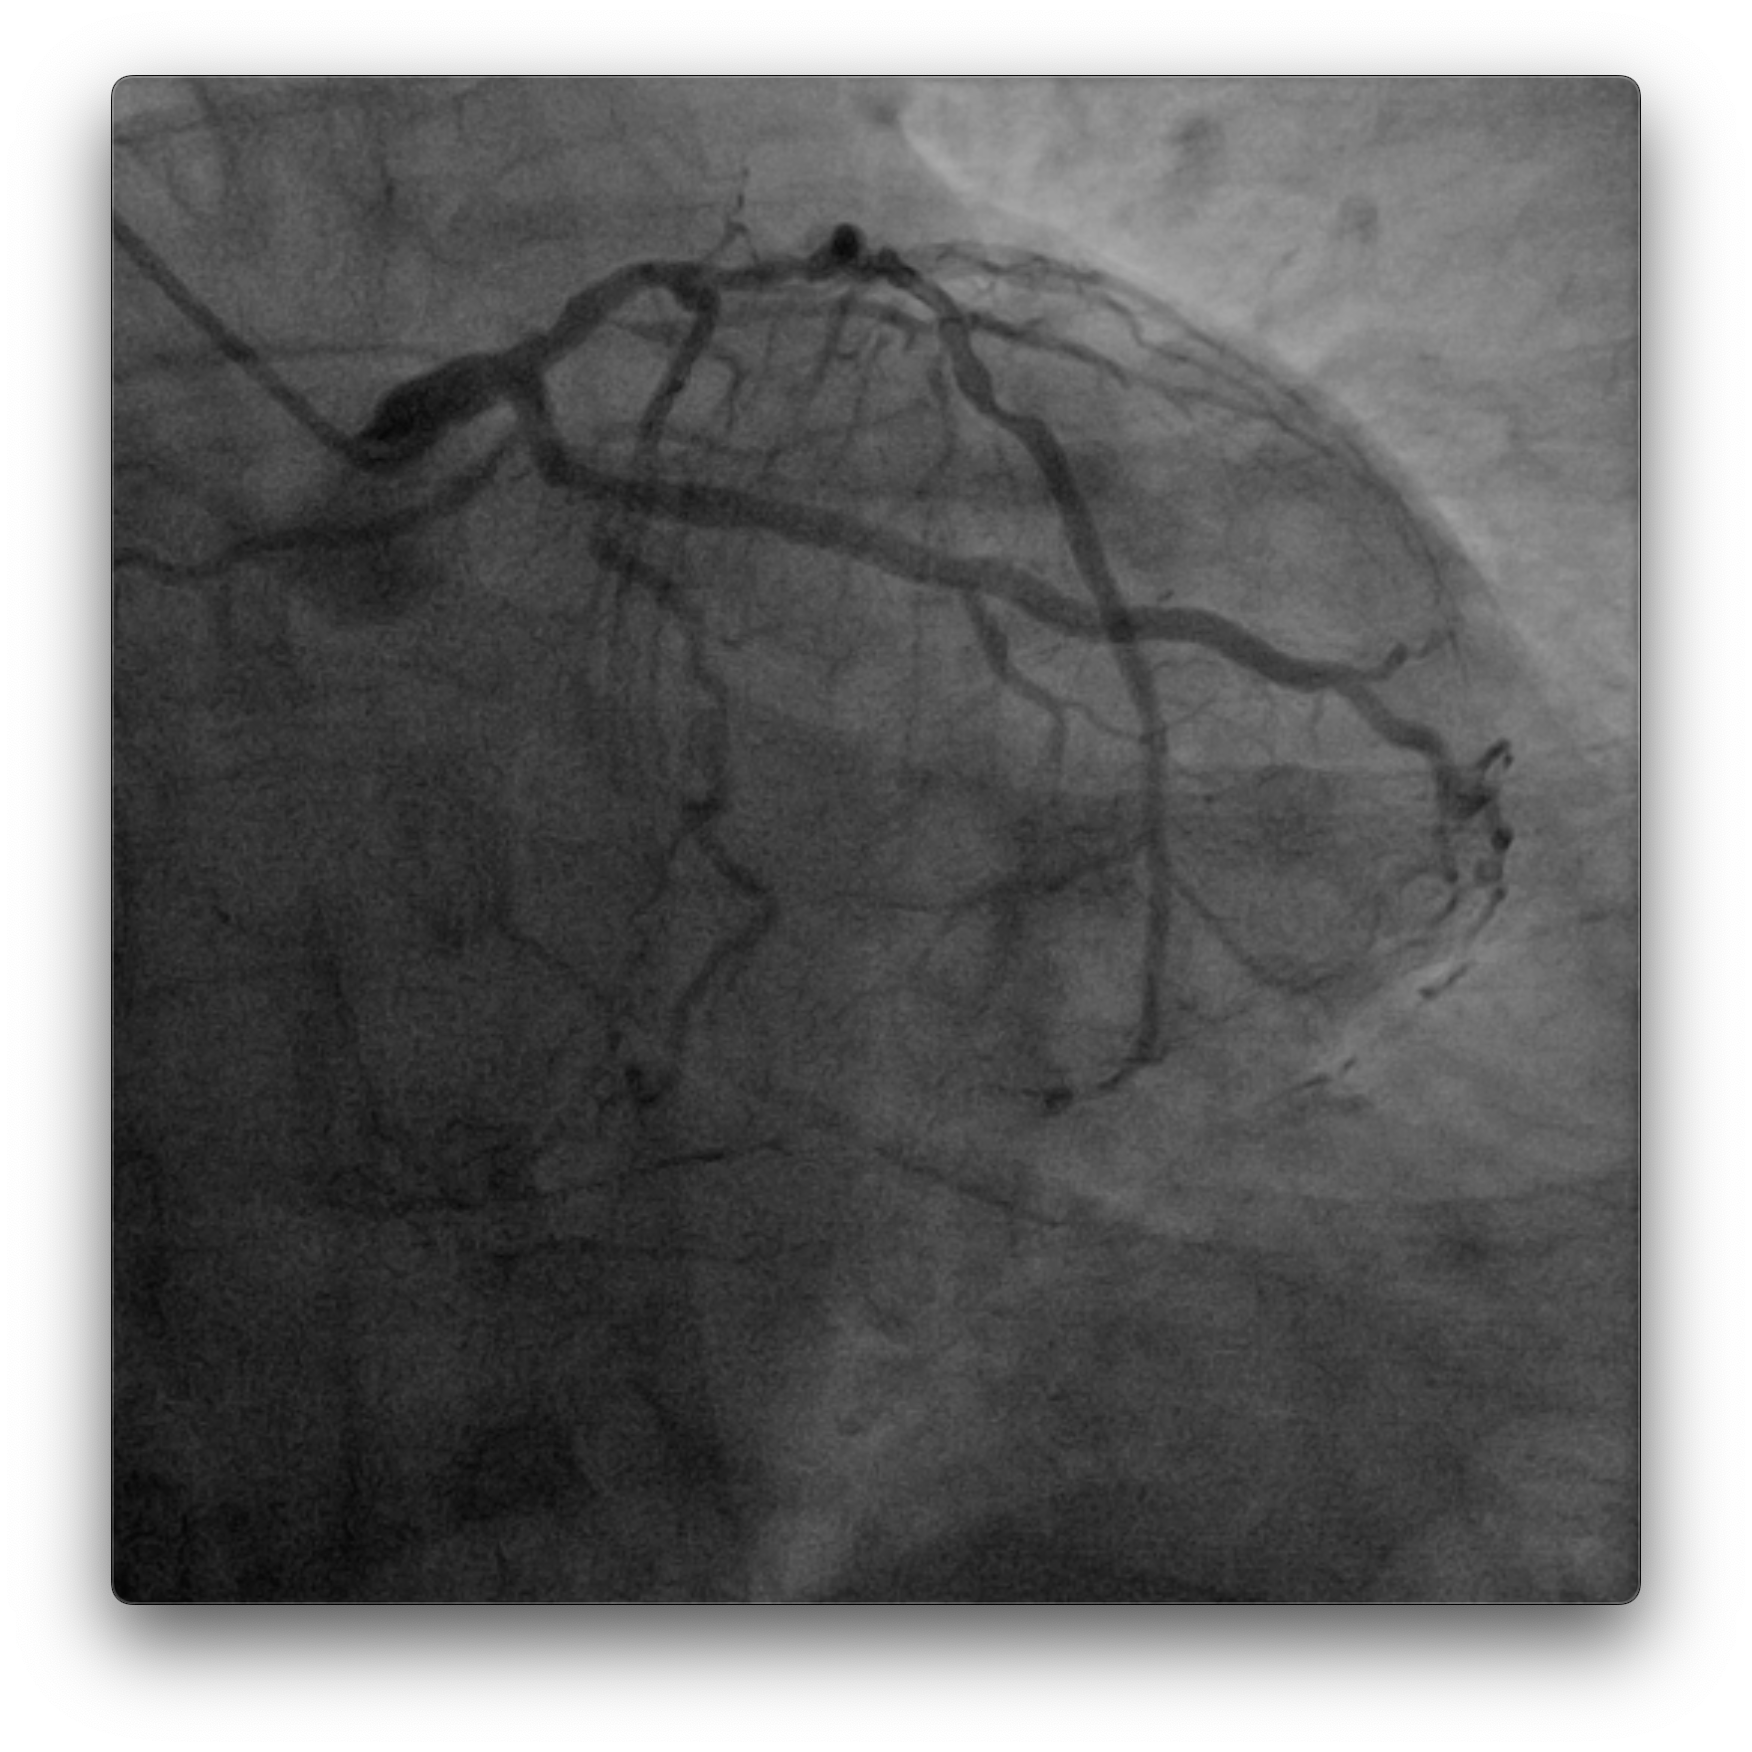

Dominant right coronary artery (RCA) with a heavily calcified, diffusely diseased segment extending from the ostium to the distal portion. The left anterior descending (LAD) and left circumflex (LCx) arteries show irregular but non-significant stenoses

PCI to RCA : Canulation using guiding catheter AL 0.75/7Fr, heparin was administered. Workhorse wire to distal PL. Initial attempt with a 1.5 ¡¿ 15 mm balloon failed to cross the distal lesion and subsequently ruptured. Rotational atherectomy was performed using a 1.5 mm burr at 160–180k rpm with three runs and one polishing pass. A 2.0 ¡¿ 15 mm semi-compliant balloon was then advanced from distal to proximal segments with the assistance of a guide extension catheter.IVUS evaluation demonstrated a 360¡Æ circumferential calcium arc and multiple calcium nodules extending from proximal to distal RCA. Lesion preparation was continued using sequential scoring balloon 2.0 mm and NC 2.5 mm, and cutting balloon 3.0 mm at high pressure. A ¡°dogbone¡± appearance was noted with the cutting balloon at the proximal RCA. An intravascular lithotripsy (IVL) balloon 3.0 mm was then applied to both distal and proximal RCA, delivering a total of 120 pulses (up to 8 atm).Repeat IVUS confirmed adequate calcium modification and optimal lesion preparation. Three overlapping drug-eluting stents (DES) were deployed: 3.0 ¡¿ 38 mm (distal–mid RCA), 3.5 ¡¿ 32 mm (mid RCA), and 4.0 ¡¿ 22 mm (ostial–proximal RCA), followed by sequential post-dilatation up to 4.0 mm. Final IVUS confirmed good stent apposition and expansion, with a minimal stent area of 6.36 mm©÷ at the distal RCA. TIMI 3 flow was achieved. Total contrast volume: 160 mL, Fluoroscopy time: 01:09:34 minutes, DAP: 232 Gy¡¤cm©÷